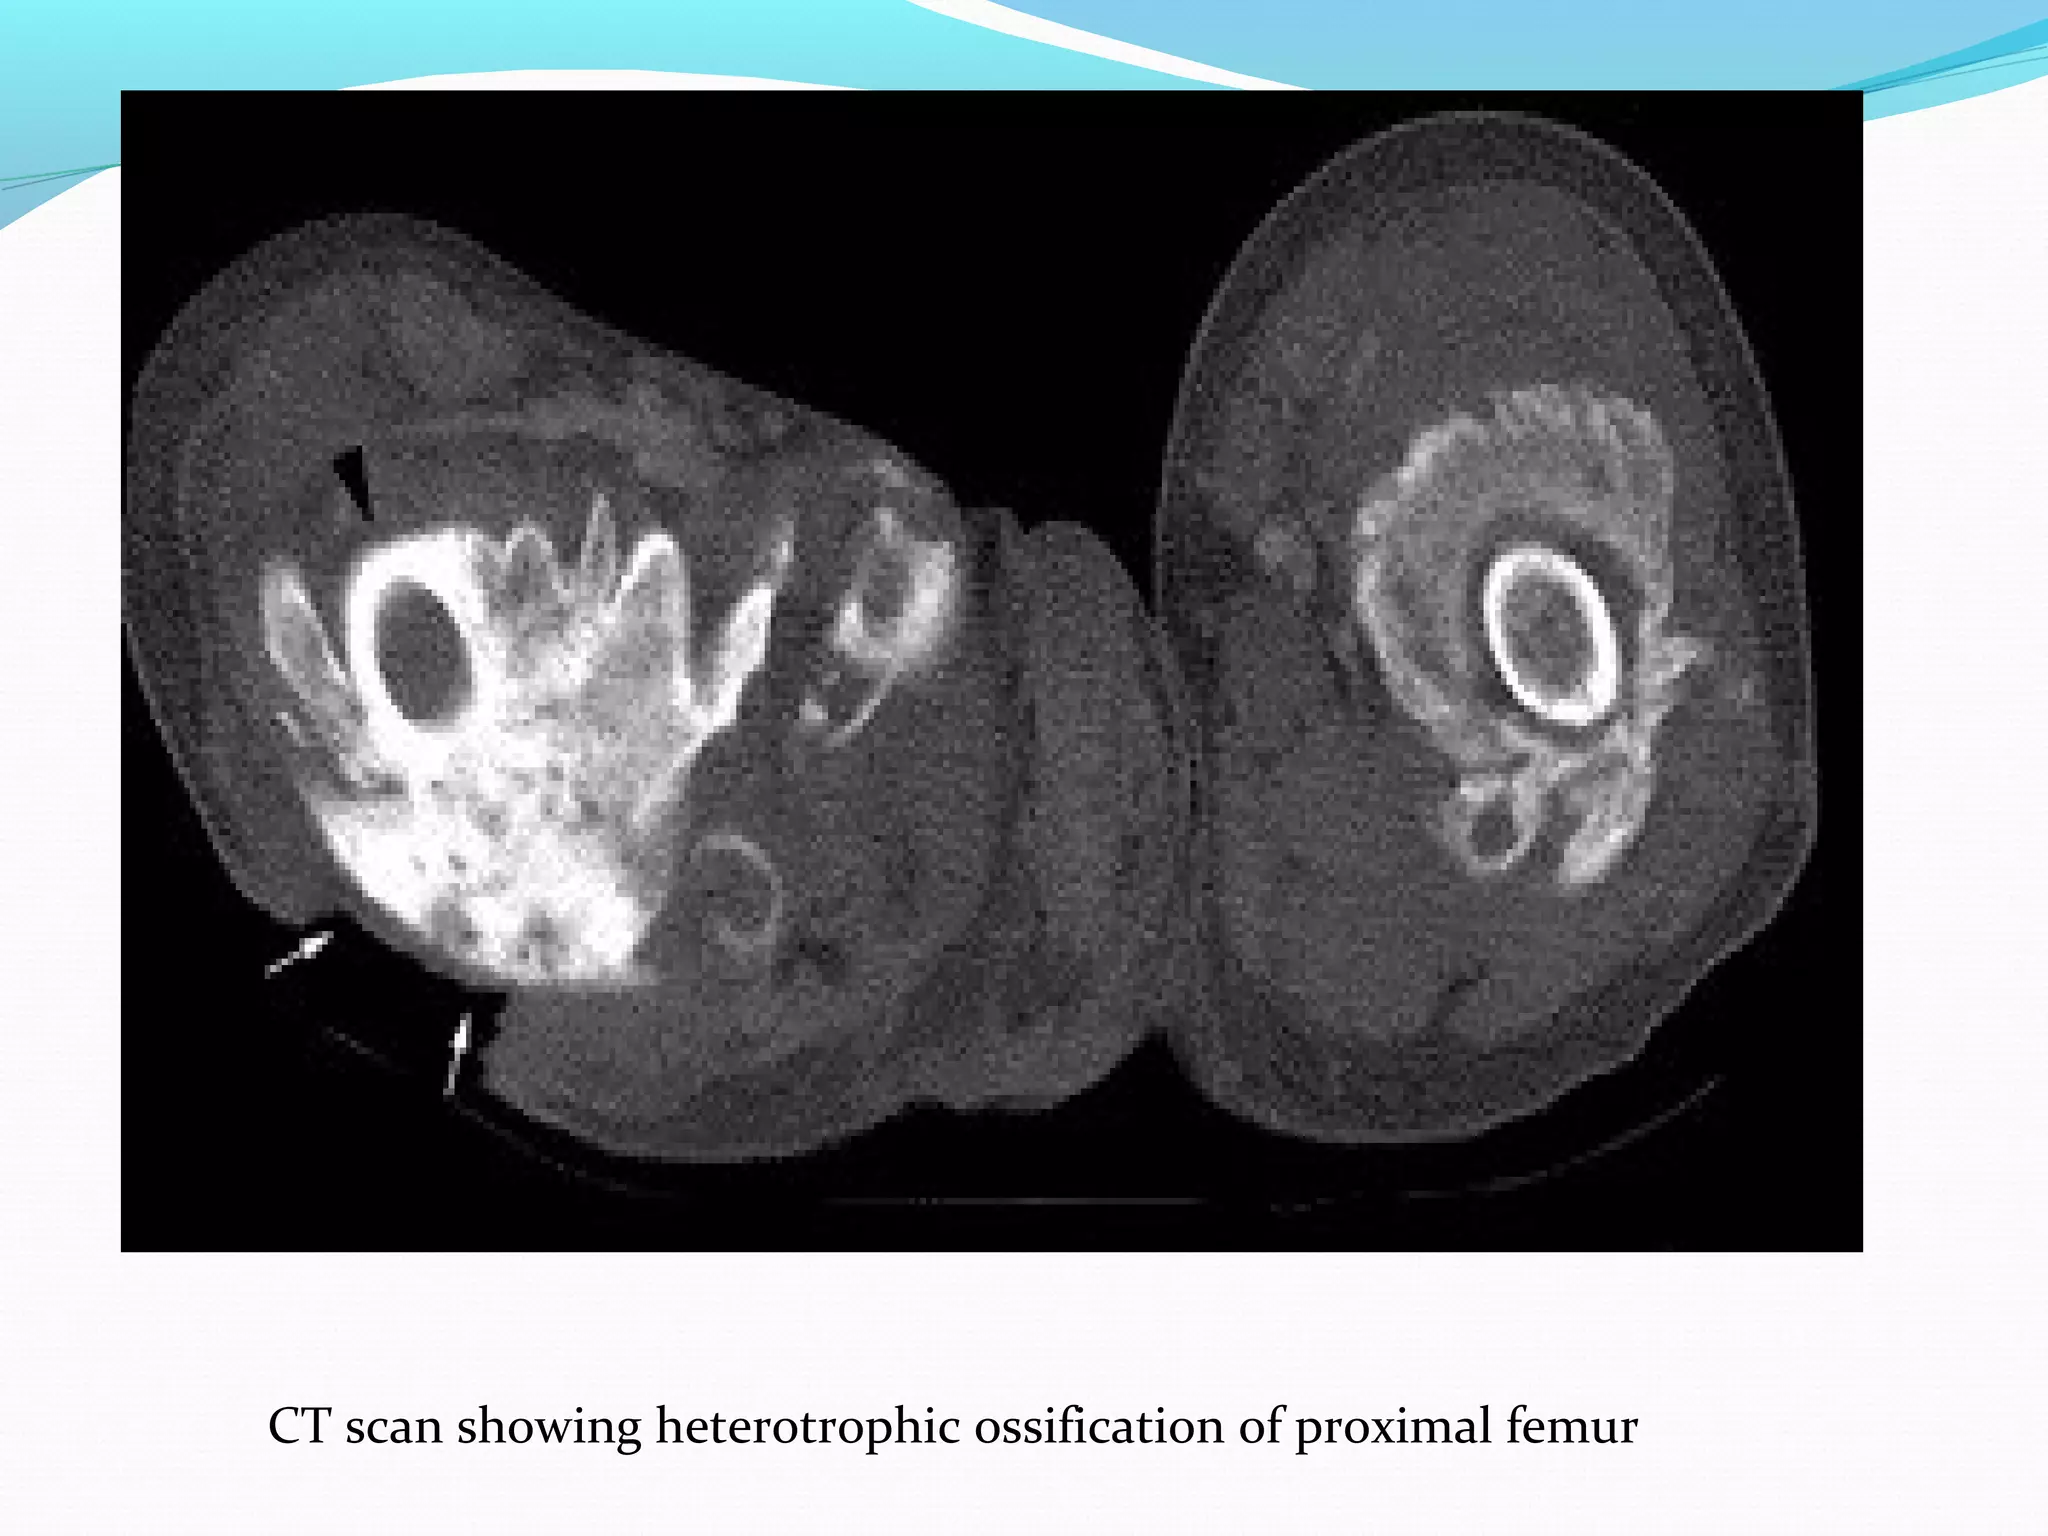

Radiography, MRI, CT Scan:

all have low specificity in early stage of disease process

better for detection in later stages when ossification is

more pronounced

MRI and CT are valuable pre-operative tools to determine

relationship to blood vessels and peripheral nerve

structures

HO demonstrable on radiographs 4-6 weeks post-injury

MRI better than radiograph at detecting HO in early

phases

Plain film radiographs are most commonly used due to

their simplicity and low cost.

Typical radiologic presentation of HO is circumfrential

ossification with a lucent center

CT scan showing heterotrophic ossification of proximal femur